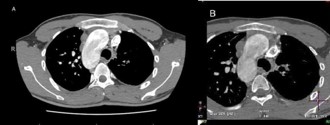

CT angiogram of chest shows complex cardiac disease including right-sided aortic arch (Figure 1), ventricular septal defect and overriding aorta (Figure 2). Non-visualization of the pulmonary trunk (Figure 3).

Two arterial supplies to the right lung arising from the descending aorta. A dominant one arising from the medial side that supplies the right upper lobe (Figure 3). Another smaller branch supplies the right middle and lower lobes (Figure 4).

Small blind-ended artery arising from the aortic arch at the take-off point of the left brachiocephalic artery (Figure 5) with non-visualization of left main pulmonary artery (Figure 3A). Multiple small arterial collaterals at the left hilum supplying the relatively hypo-plastic left lung (Figure 3A).

Right ventricular dilatation with myocardial hypertrophy (Figure 4).

Figure 2: Contrast-enhanced reconstructed 3 chambers view of the heart showing a ventricular septal defect and overriding aorta.

Figure 3: Contrast-enhanced CT chest axial (A), sagittal and coronal (B) views, showing an arterial supply to the right upper lobe arising from the descending aorta. Also there is an absent left pulmonary artery with multiple small collaterals at the left hilar region. Relative hypo-plastic left lung.